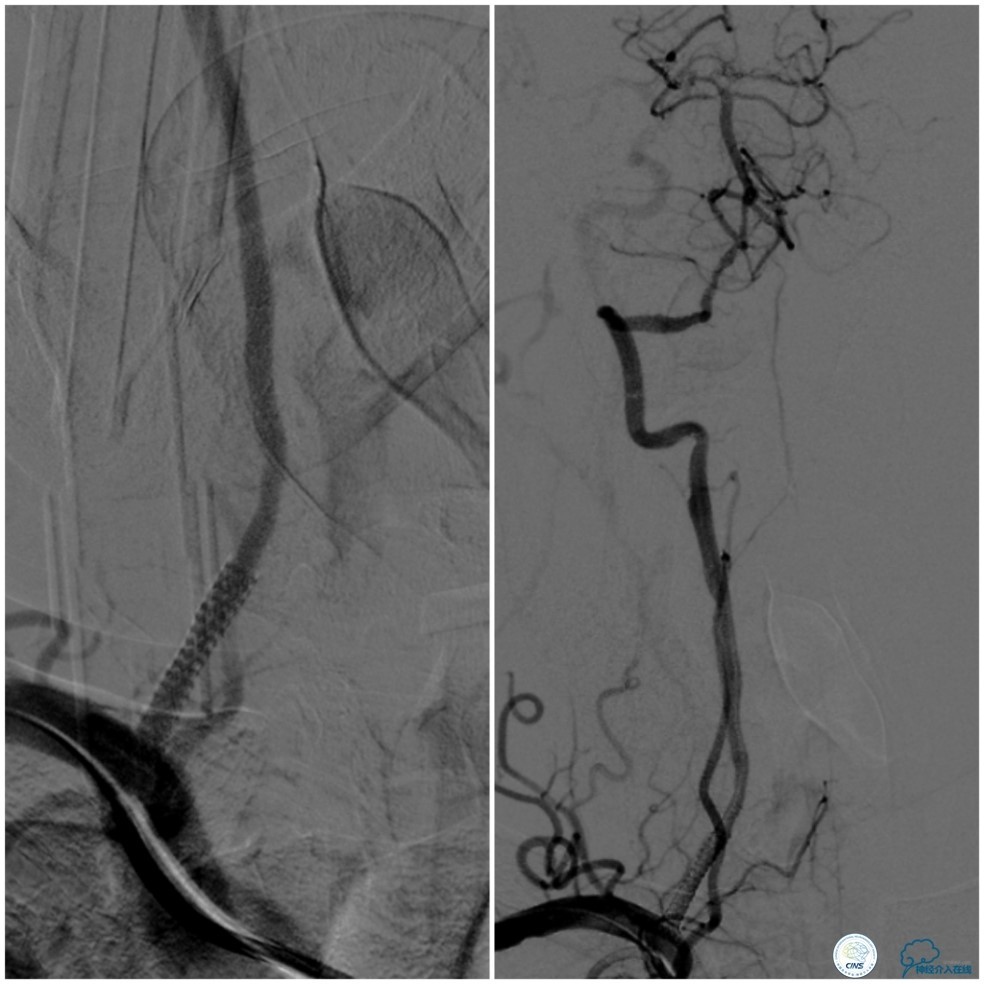

此时多体外投照显示右椎V4-基底动脉极重度狭窄,几近闭塞(图12)。

图12

Transend(0.014″300cm)微导丝+Echelon-10微导管,小心通过右椎动脉V4段病变后置于右大脑后动脉P1段(图13)。

图13

Gateway球囊(1.5mm×15mm)于狭窄段扩张后放置Wingspan支架(2.5 mm×15mm),撤出微导丝后造影,局部狭窄率50%,支架内中远段见细小充盈缺损,考虑急性血栓形成,予以欣维宁5ml动脉内缓慢注射未见好转(图14)。

图14

遂再次将Transend微导丝送至右大脑后动脉P1段,使用Gateway球囊(2.0mm×15mm)于支架最狭窄处后扩张(图15)。

图15

其后造影显示支架贴壁良好,远端血管显影好,前向血流TICI3级(图16)。

图16

缓慢回撤6F导引导管至锁骨下动脉,造影显示右椎V1段支架无移位,前向血流正常(图17)。

图17